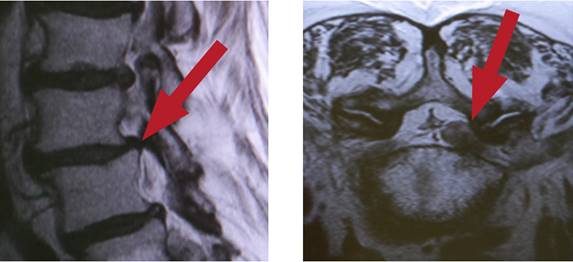

Le canal rachidien est un canal osseux délimité par les corps vertébraux, Les disques intervertébraux, les arcs vertébraux; contenant la moelle épinière et les nerfs spinaux. les nerfs spinaux, d'une part, transmettent des informations sensorielles au cerveau depuis l'extérieur du corps et, d'autre part, sont responsables de la commande des fonctions musculaires. Avec l'âge, la colonne vertébrale présente des signes d'usure largement normaux, des rétrécissements peuvent apparaître dans le canal vertébral lui-même ou dans les trous intervertébraux. Cela peut comprimer ou pincer les nerfs, et provoquer des douleurs ou des troubles sensoriels. Ce tableau clinique est appelé sténose du canal rachidien ou sténose vertébrale.

Comment diagnostique-t-on la sténose du canal rachidien?

• Imagerie par résonance magnétique (IRM)